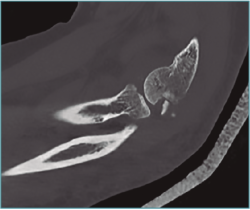

En todos los casos hemos solicitado una tomografía axial computarizada (TAC) 3D previa a la intervención, lo que es de gran utilidad para preparar la cirugía y saber dónde y cuántos osteofitos y cuerpos libres vamos a resecar (Figuras 1 y 2; Vídeo, minutos 0-1:36).

Figura 1. A: tomografía axial computarizada bidimensional (TAC); B: TAC 3D para valorar la presencia, el tamaño y la localización de osteofitos y cuerpos libres.